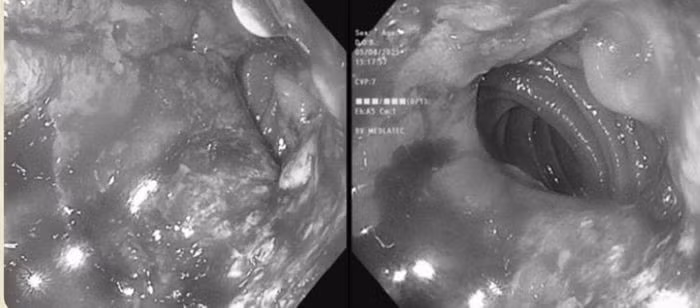

Kết quả nội soi dạ dày cho thấy dạ dày của ông đã bị cắt bán phần từ trước. Phần dạ dày còn lại và miệng nối bị phù nề, xung huyết, kèm theo nhiều vết loét dễ chảy máu khi bơm hơi. Các bác sĩ đã tiến hành sinh thiết bốn mảnh tại bờ ổ loét để xét nghiệm mô bệnh học.

Kết quả sinh thiết cho thấy các tuyến dạ dày có dấu hiệu bất thường: Nhân tế bào lớn, kiềm tính, màng nhân méo mó, hạt nhân nổi rõ. Dựa trên những phát hiện này, bác sĩ chẩn đoán ông M. mắc ung thư biểu mô tuyến dạ dày.